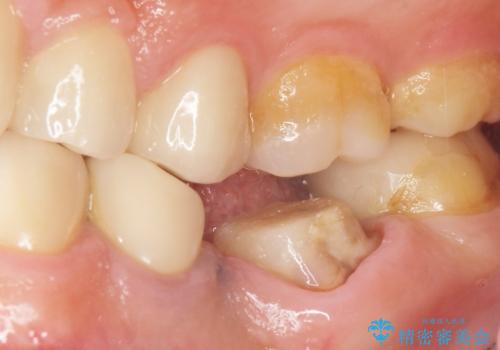

- 奥歯の被せ物をセラミックにしたいとご希望され、来院された患者様です。

左下の奥歯(左下6)の劣化した白い被せ物と金属の土台を除去し、セラミッククラウンによる補綴治療を行いました。